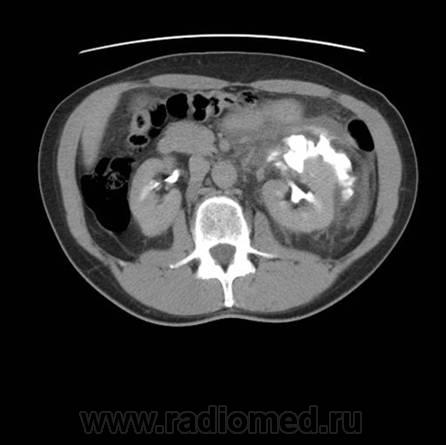

Травма. Боли в области поясницы.

Травматическое повреждение левой, по всей видимости, лоханки с разрывом и затеками контрастного препарата и мочи...